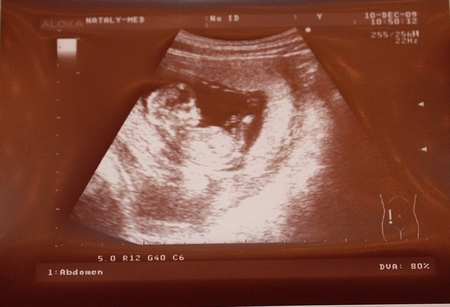

По - тихоньку становимся похожи на человечка: